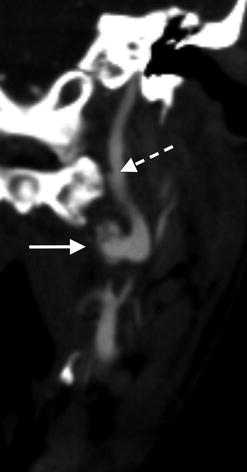

Axial CTA image through the neck in a 24-year-old male following blunt motor vehicle trauma shows a psuedoaneurysm (dashed arrow) arising from the medial aspect of the cervical left internal carotid artery (arrow)

Coronal CTA image reveals an intimal dissection flap (dashed arrow) distal to the site of pseudoaneurysm formation (arrow)

3D volumetric CTA image of the internal carotid artery with external carotid artery branches removed reveals irregular contour of the ICA pseudoaneurysm (arrow). More distally, ICA dissection manifests as focal contour abnormality of the vessel (dashed arrow)